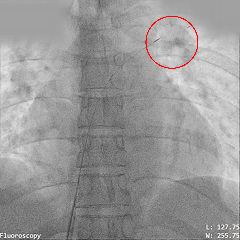

释放氧化膜封堵器左右盘面

牵拉试验封堵器稳定

释放封堵器

封堵器稳固夹持

本例为一例房间隔缺损(ASD)患者,术前彩超显示房间隔中部回声缺失,四腔心观缺损间距约1.08 cm,彩色多普勒可见左向右分流,流速曲线呈双期湍流,术前复测缺损为1.2 cm,经综合考虑,最终植入22规格MemoCarna氧化膜ASD封堵器。术中应用PannaWire®多功能导丝实现高效过隔,该导丝凭借其独特的梭形头端与分段结构设计,过程充当“泥鳅导丝+加硬导丝”功能,一丝多用,实现零交换操作,显著减少器械交换步骤,提升了手术效率;同时,梭形头端可固定在肺静脉处,避免出现导丝脱出导致重新建立输送轨道。封堵器展开后形态良好,稳定夹持于房间隔两侧,无残余分流。该病例充分验证了PannaWire®多功能导丝在简化ASD封堵流程、提升操作安全性及效率方面的临床优势。